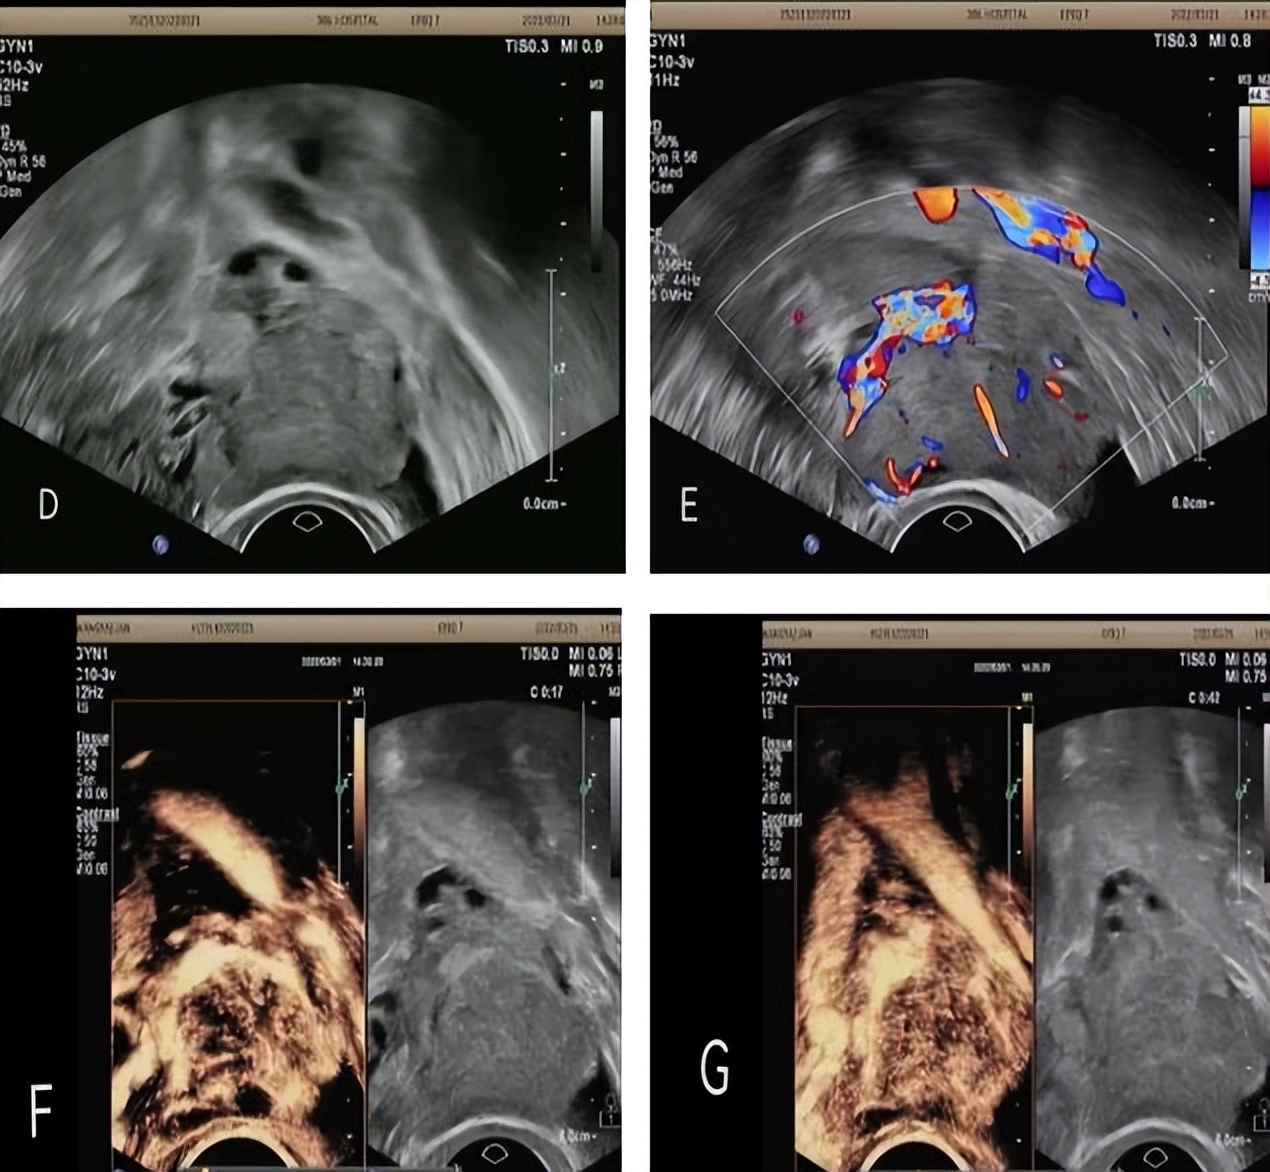

病例2:女,46岁,主因“结肠息肉”入院。常规超声于左附件区探及不均质高回声,大小约4.9x3.3cm。超声造影:病灶早于左卵巢呈不均匀快速高增强,可见血管迂曲走行穿入瘤体,以血管为中心向瘤体内部灌注,晚期造影剂消退早于卵巢。超声造影提示:左附件区实性占位性病变(倾向恶性)。手术病理:左侧卵巢内膜样腺癌,呈中分化。

病例3:女,73岁,主因“下腹部触痛、外阴疼痛一周”入院。常规超声:子宫右前方囊性包块,其内可见粗细不等的分割,范围约17.1x10.0cm。静脉超声造影:增强早期囊壁及囊内分隔上可见造影剂灌注显影早于子宫肌层,达峰时囊壁及分隔上灌注区域呈高增强,增强晚期,囊壁及分隔上造影剂消退迟于子宫肌层,呈持续性低增强。超声造影提示:左卵巢粘液性囊腺瘤(可疑交界性)。术后病理:左卵巢粘液性囊腺瘤(局灶区域呈上皮样增生)。